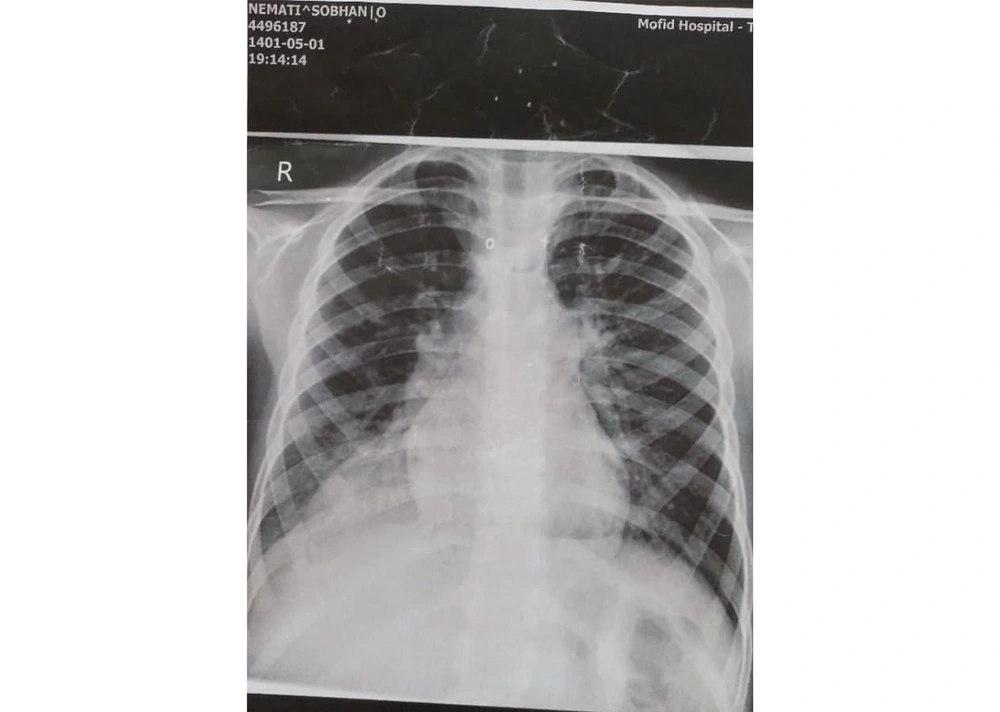

Chest and abdominal X-rays were performed to evaluate the abdominal pain and cough. The CXR revealed a suspicious lung finding (Figure 2). A computed tomography (CT) scan was requested to assess the lung lesion, and a hydatid cyst was incidentally diagnosed in the right lower lobe (Figure 3). The patient was treated with antibiotics for the UTI, and pre-surgical evaluations for the hydatid cyst were conducted. A cardiac consultation revealed mild pulmonary hypertension (systolic pulmonary arterial pressure: 40 - 45 mmHg), right ventricular dilation, right atrial dilation, and moderate tricuspid regurgitation on echocardiography. The CT angiography confirmed the diagnosis of PAPVC.

In this report, we present a 6-year-old boy with a history of recurrent nephrolithiasis and UTI. His mother also reported occasional coughs during admission. A CXR revealed a doubtful halo, prompting a lung CT scan, which diagnosed hydatidosis. During preparation for hydatidosis surgery, cardiac abnormalities were found on the electrocardiogram, leading to a diagnosis of PAPVC. The patient had no complaints related to cardiac function; both hydatidosis and PAPVC were incidentally diagnosed.

Data on the incidence rates of hydatidosis are regional. A study by Saghafipour et al. reported an incidence rate of 6.81 per 100,000 people over 8 years (16). Mustapayeva et al. found the incidence rate of hydatidosis in Kazakhstan from 2007 to 2016 to be ≤ 0.1% (17). Simple chest radiography (CXR) is the first diagnostic modality for pulmonary hydatidosis. If findings are inconclusive, a pulmonary CT scan can aid in detection (18). We observed a halo in the CXR of our case, prompting a CT scan that confirmed pulmonary hydatidosis. Surgery is the main treatment for pulmonary hydatidosis, with the surgical technique depending on factors such as cyst location, surgeon’s decision, and cyst wall tissue (19, 20). Our case underwent surgery for lung hydatidosis.